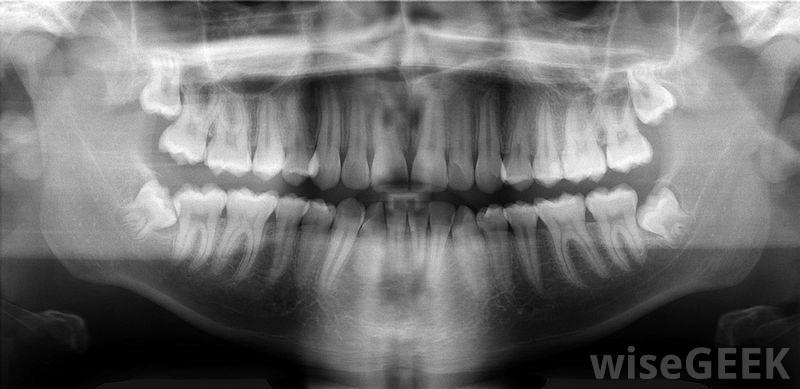

牙骨质覆盖在牙根表面,只有通过X光才能看到。牙科领域的专家使用流体力学强调珐琅质和牙骨质防止牙齿变得过于敏感的理论。牙本质是牙齿上珐琅质或牙骨质所在的部分。珐琅质是最坚硬的牙齿材料,覆盖了牙冠,牙齿在口腔中可见的部分。牙骨质覆盖着牙根的表面,牙骨质被嵌入其中在骨中。如果牙本质没有被这些材料覆盖,并且由于牙齿缺陷而暴露在外,患者会感到敏感。